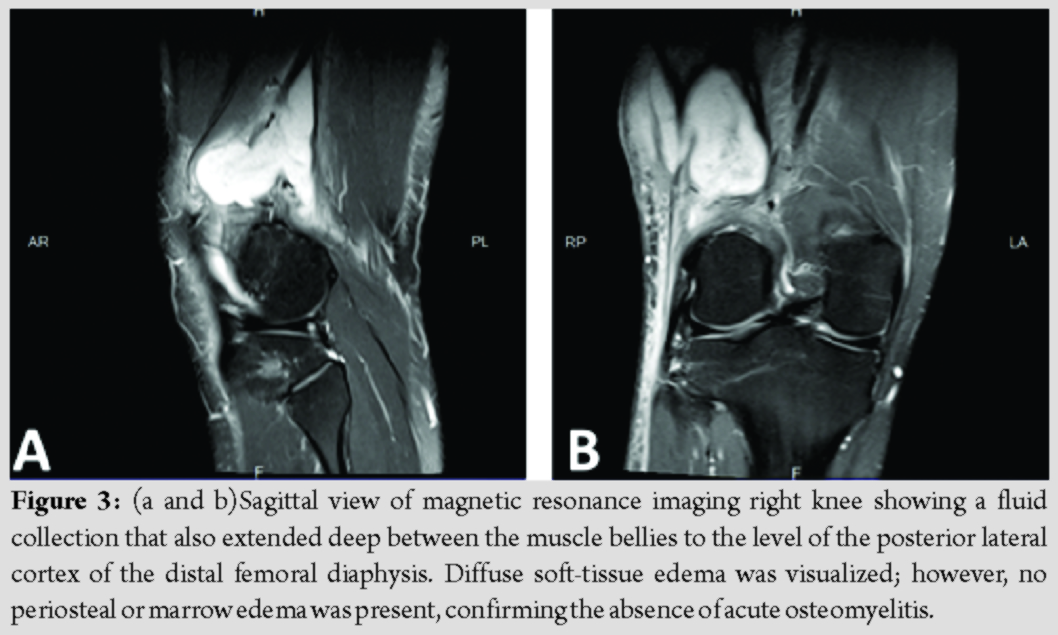

At presentation, the patient stated that this episode did not resolve with rest or anti-inflammatory medication. He reported the drainage had been ongoing for 2 weeks and appeared to come from a punctum in the center of the swelling, but denied any fever, chills, sharp pain, change in sensation, or restriction in active or passive range of motion. X-ray showed no acute OM or fractures (Fig. 1a and b). Magnetic resonance imaging (MRI) of the knee revealed 6.8 × 5.3 × 8.5cm septated fluid collection consistent with a large abscess extending from the subcutaneous adipose tissue along the lateral aspect of the thigh through a perforation in the fascia posterior to the vastus lateralis and tensor fascia lata and anterior to the biceps femoris (Fig. 2a-d). The fluid collection also extended deep between the muscle bellies to the level of the posterior lateral cortex of the distal femoral diaphysis. Diffuse soft-tissue edema was visualized; however, no periosteal or marrow edema was present, confirming the absence of acute OM (Fig. 3a and b).